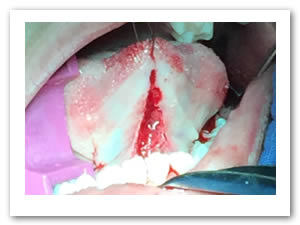

• Se eliminó el frenillo en su totalidad  con la ayuda de tijeras iris recta y hoja de bisturí del No. 15 así como todo el tejido residual fibroso correspondiente al frenillo. Se realizó genioplastia con pinza de mosco y disección roma para liberar adecuadamente la inserción frénica hasta la cara lingual de los incisivos inferiores. (Figuras  7, 8 y 9)

Figuras 7 y 8. Eliminación total del frenillo y genioplastia

Figura 9. Resultado obtenido después de genioplastia